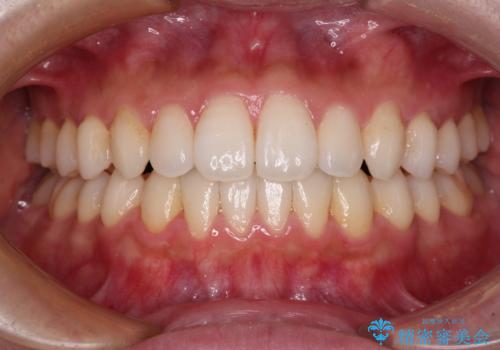

前歯の捻れを改善 インビザラインによる矯正治療